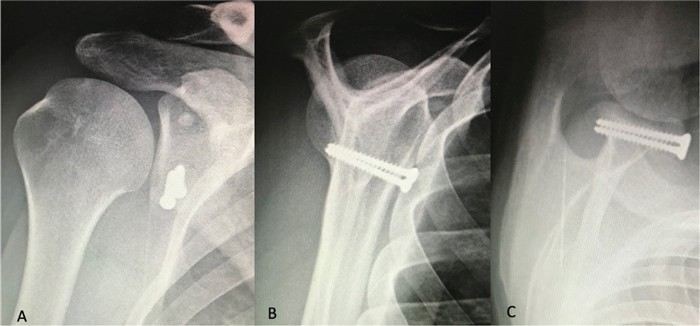

Суть операции Латарже заключается в том, что хирург с помощью специальной процедуры стабилизирует клювовидный отросток, что уменьшает вероятность повторных вывихов. Призывникам, которым предстоит операция, важно понимать, что после вмешательства потребуется длительная реабилитация, включающая ношение ортеза, применение компрессов и выполнение определённых упражнений. Эти меры помогут избежать осложнений и ускорить восстановление. Важно, что процесс реабилитации также влияет на призывную пригодность.

Операция Латарже — это один из методов стабилизации сустава. Однако даже после такого вмешательства необходимо соблюдать рекомендации врача, проходить реабилитацию и следить за состоянием сустава. Послеоперационный период может занять несколько месяцев, и в этот период могут быть рекомендованы компрессы, ношение ортеза и ограничение физической активности. В случае осложнений или если вывихи продолжаются после операции, призывнику могут предоставить отсрочку от службы или признать его негодным для выполнения воинской обязанности.